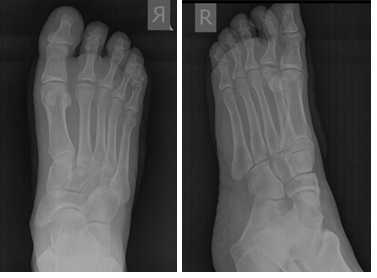

Кожа ушита внутрикожным швом. В послеоперационном периоде пациент использовал специальную обувь с разгрузкой переднего отдела стопы на протяжении 2 недель, с дальнейшим переходом к ношению обычной обуви. С целью обезболивания были назначены НПВП, а также холод местно по 30 минут каждые 4 часа на протяжении 10 дней. Ниже представлены рентгенограммы после операции.